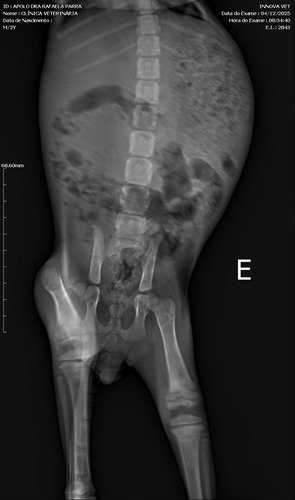

Eu fui encontrado em um estacionamento aqui em Santa Adélia, sentindo muita dor e com dificuldade para andar. Quando me levaram ao veterinário, descobriram que meu fêmur está quebrado.Para eu voltar a andar e ter uma vida sem dor, eu preciso fazer uma cirurgia urgente.